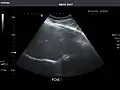

Kidneys: Right and left kidneys measure 11.5 cm and 12 cm in length respectively. No hydronephrosis. Small left lower pole kidney cyst.

Left kidney